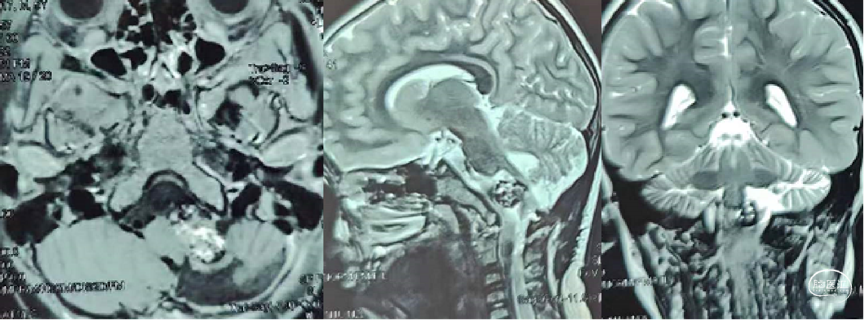

脑血管造影显示左椎动脉巨大血栓化蛇形动脉瘤,累及小脑后下动脉(PICA)。

头颅MRI

血栓化动脉瘤瘤体巨大,虽无明显相关症状,但影像显示瘤体对脑干及周围神经组织压迫明显,需行动脉瘤孤立术,减轻瘤体占位效应。